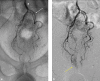

Emborrhoid: Rectal Artery Embolization for Hemorrhoid Disease

- Vidal V, Louis G, Bartoli J M, Sielezneff I. Embolization of the hemorrhoidal arteries (the emborrhoid technique): a new concept and challenge for interventional radiology. Diagn Interv Imaging. 2014;95(03):307–315. - PubMed

- Vidal V, Sapoval M, Sielezneff Y. Emborrhoid: a new concept for the treatment of hemorrhoids with arterial embolization: the first 14 cases. Cardiovasc Intervent Radiol. 2015;38(01):72–78. - PubMed

- Tradi F, Louis G, Giorgi R. Embolization of the superior rectal arteries for hemorrhoidal disease: prospective results in 25 patients. J Vasc Interv Radiol. 2018;29(06):884–8920. - PubMed